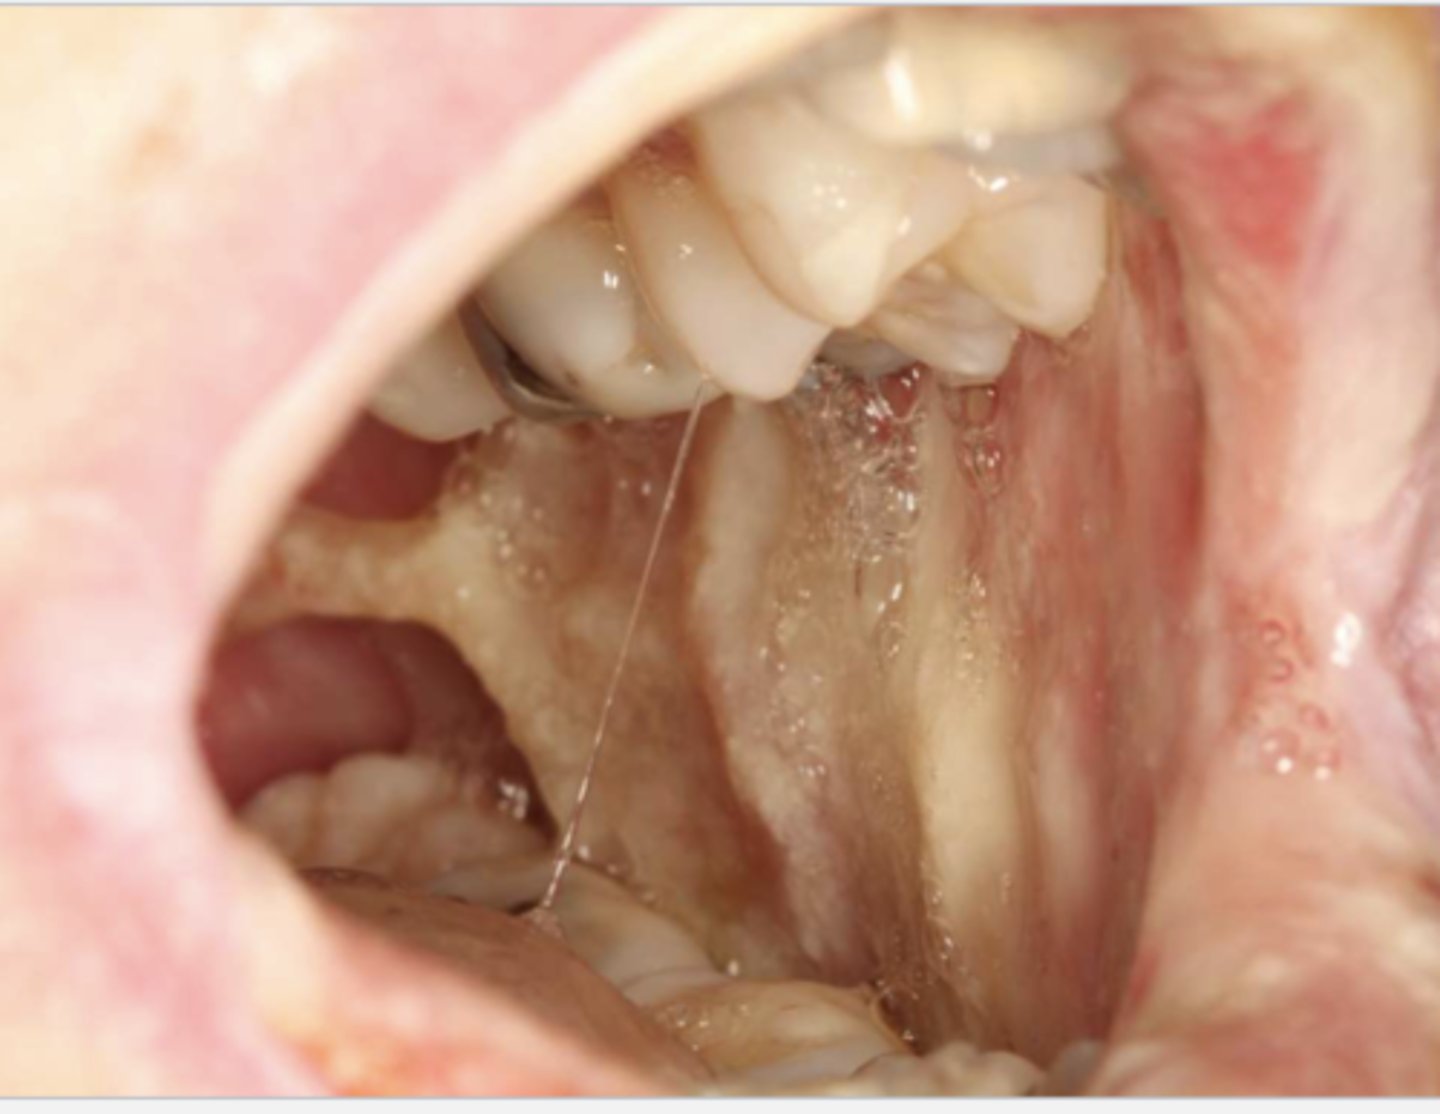

what do you suspect?

osteonecrosis

osteonecrosis/osteoradionecrosis/ MRONJ